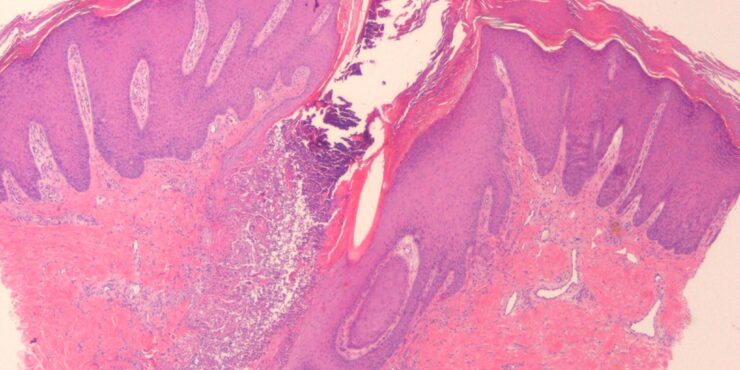

Keratosis follicularis = التقران الجرابي Keratosis Pilaris This common persistent condition characteristically affects the lateral aspect of the arms, thighs, and buttocks. Keratotic follicular papules, sometimes with surrounding erythema, are present. They are usually asymptomatic. Keratosis pilaris may be seen in association with ichthyosis vulgaris and appears to be more common in patients with atopic […]